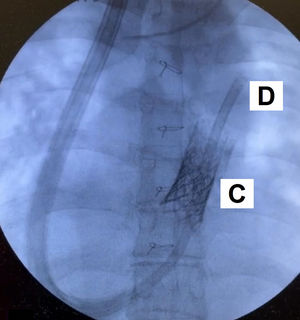

Hombre de 33 años con síndrome de Rendu-Osler-Weber y estenosis aórtica congénita corregida con cirugía de Ross. Presentaba estenosis grave del homoinjerto con implante transcatéter de prótesis pulmonar Melody (Medtronic, Mineápolis, MN, EE. UU.), e hipertensión pulmonar poscapilar grave mixta con disfunción ventricular derecha severa, siendo incluido en lista de trasplante cardiopulmonar. Ingresó por insuficiencia respiratoria, que requirió ECMO veno-venosa percutánea. En la figura 1 se aprecia la cánula de drenaje femoral en la cava inferior (A), la de retorno yugular en la aurícula derecha (B), y la prótesis Melody en la arteria pulmonar (C). Se precisó hemodiafiltración por fallo derecho. Al quinto día se decidió el cambio a cánula de doble luz ProtekDuo (LivaNova, Londres, Reino Unido) como asistencia derecha con oxigenador puente al trasplante cardiopulmonar. En la figura 2 se observa la cánula ProtekDuo (D) atravesando la prótesis Melody (C), con el drenaje en la aurícula derecha y el extremo distal de retorno en la arteria pulmonar. Se retiró la hemodiafiltración a la semana. Realizaba rehabilitación en espera del trasplante. No obstante, presentó sangrado digestivo incoercible, siendo exitus a las 2 semanas.